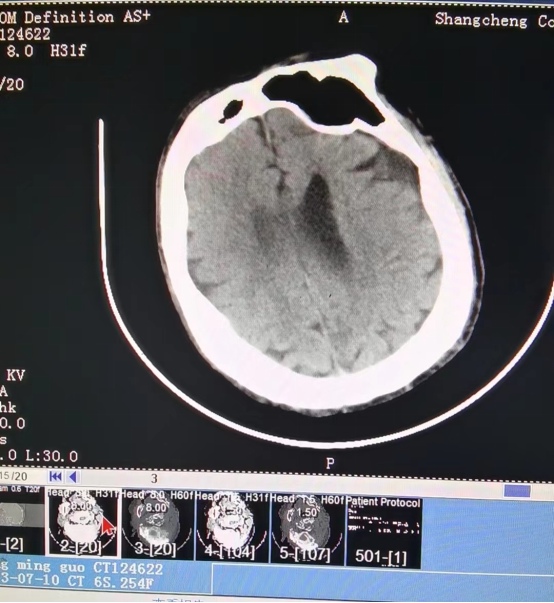

近日,55岁的冯先生突发急性脑梗死,我院卒中中心启动绿色通道,给予静脉溶栓桥接取栓治疗,成功打通堵塞的“生命管道”,患者转危为安,术后恢复良好,避免了“一人中风,全家瘫痪”的悲剧。